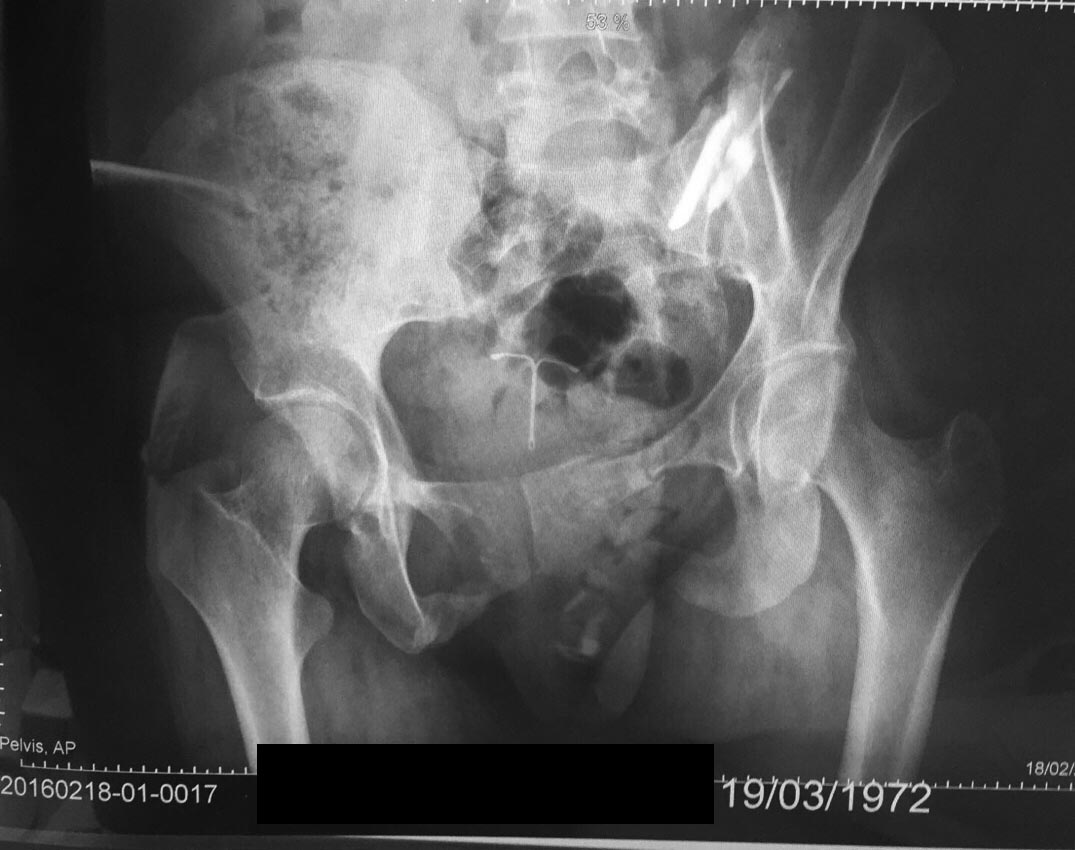

Полгода назад была политравма. Из за тяжелого состоянии не выправили нормально таз.

Нужна ли ещё операция? Посоветуйте, пожалуйста! И чем чревато такой перекос?

Болезненные ощущения в левой части области таза, точнее крестца. При длительной ходьбе боль переходит на всю левую ногу, начинается хромота. Предлагают операцию по скреплению пластиной заднего полукольца. На сколько опасны такие операции? Беспокоит ещё большие проблемы с памятью после операции

В любом случае, чтобы дать совет, надо больше информации, чем видно на одном прямом снимке. Надо увидеть inlet view, КТ.

Здравствуйте, Светлана! По одному снимку, причём в не очень правильной проекции трудно что-то решать. Необходимо полное обследование, включающее осмотр, компьютерную томографию, рентгенограммы в правильных проекциях, в том числе, возможно, функциональные. Лучше всего приехать на очную консультацию в УИТО - г.Екатеринбург, Банковский, 7, травматолого-ортопедическое отделение №1, заведующий - Рунков Алексей Владимирович, тел. +73433710993. Если соберётесь, лучше сделать где-нибудь компьютерную томографию таза и привезти с собой её результаты на диске. Толщина среза должна быть 0.5 мм. С уважением, Данил Близнец.